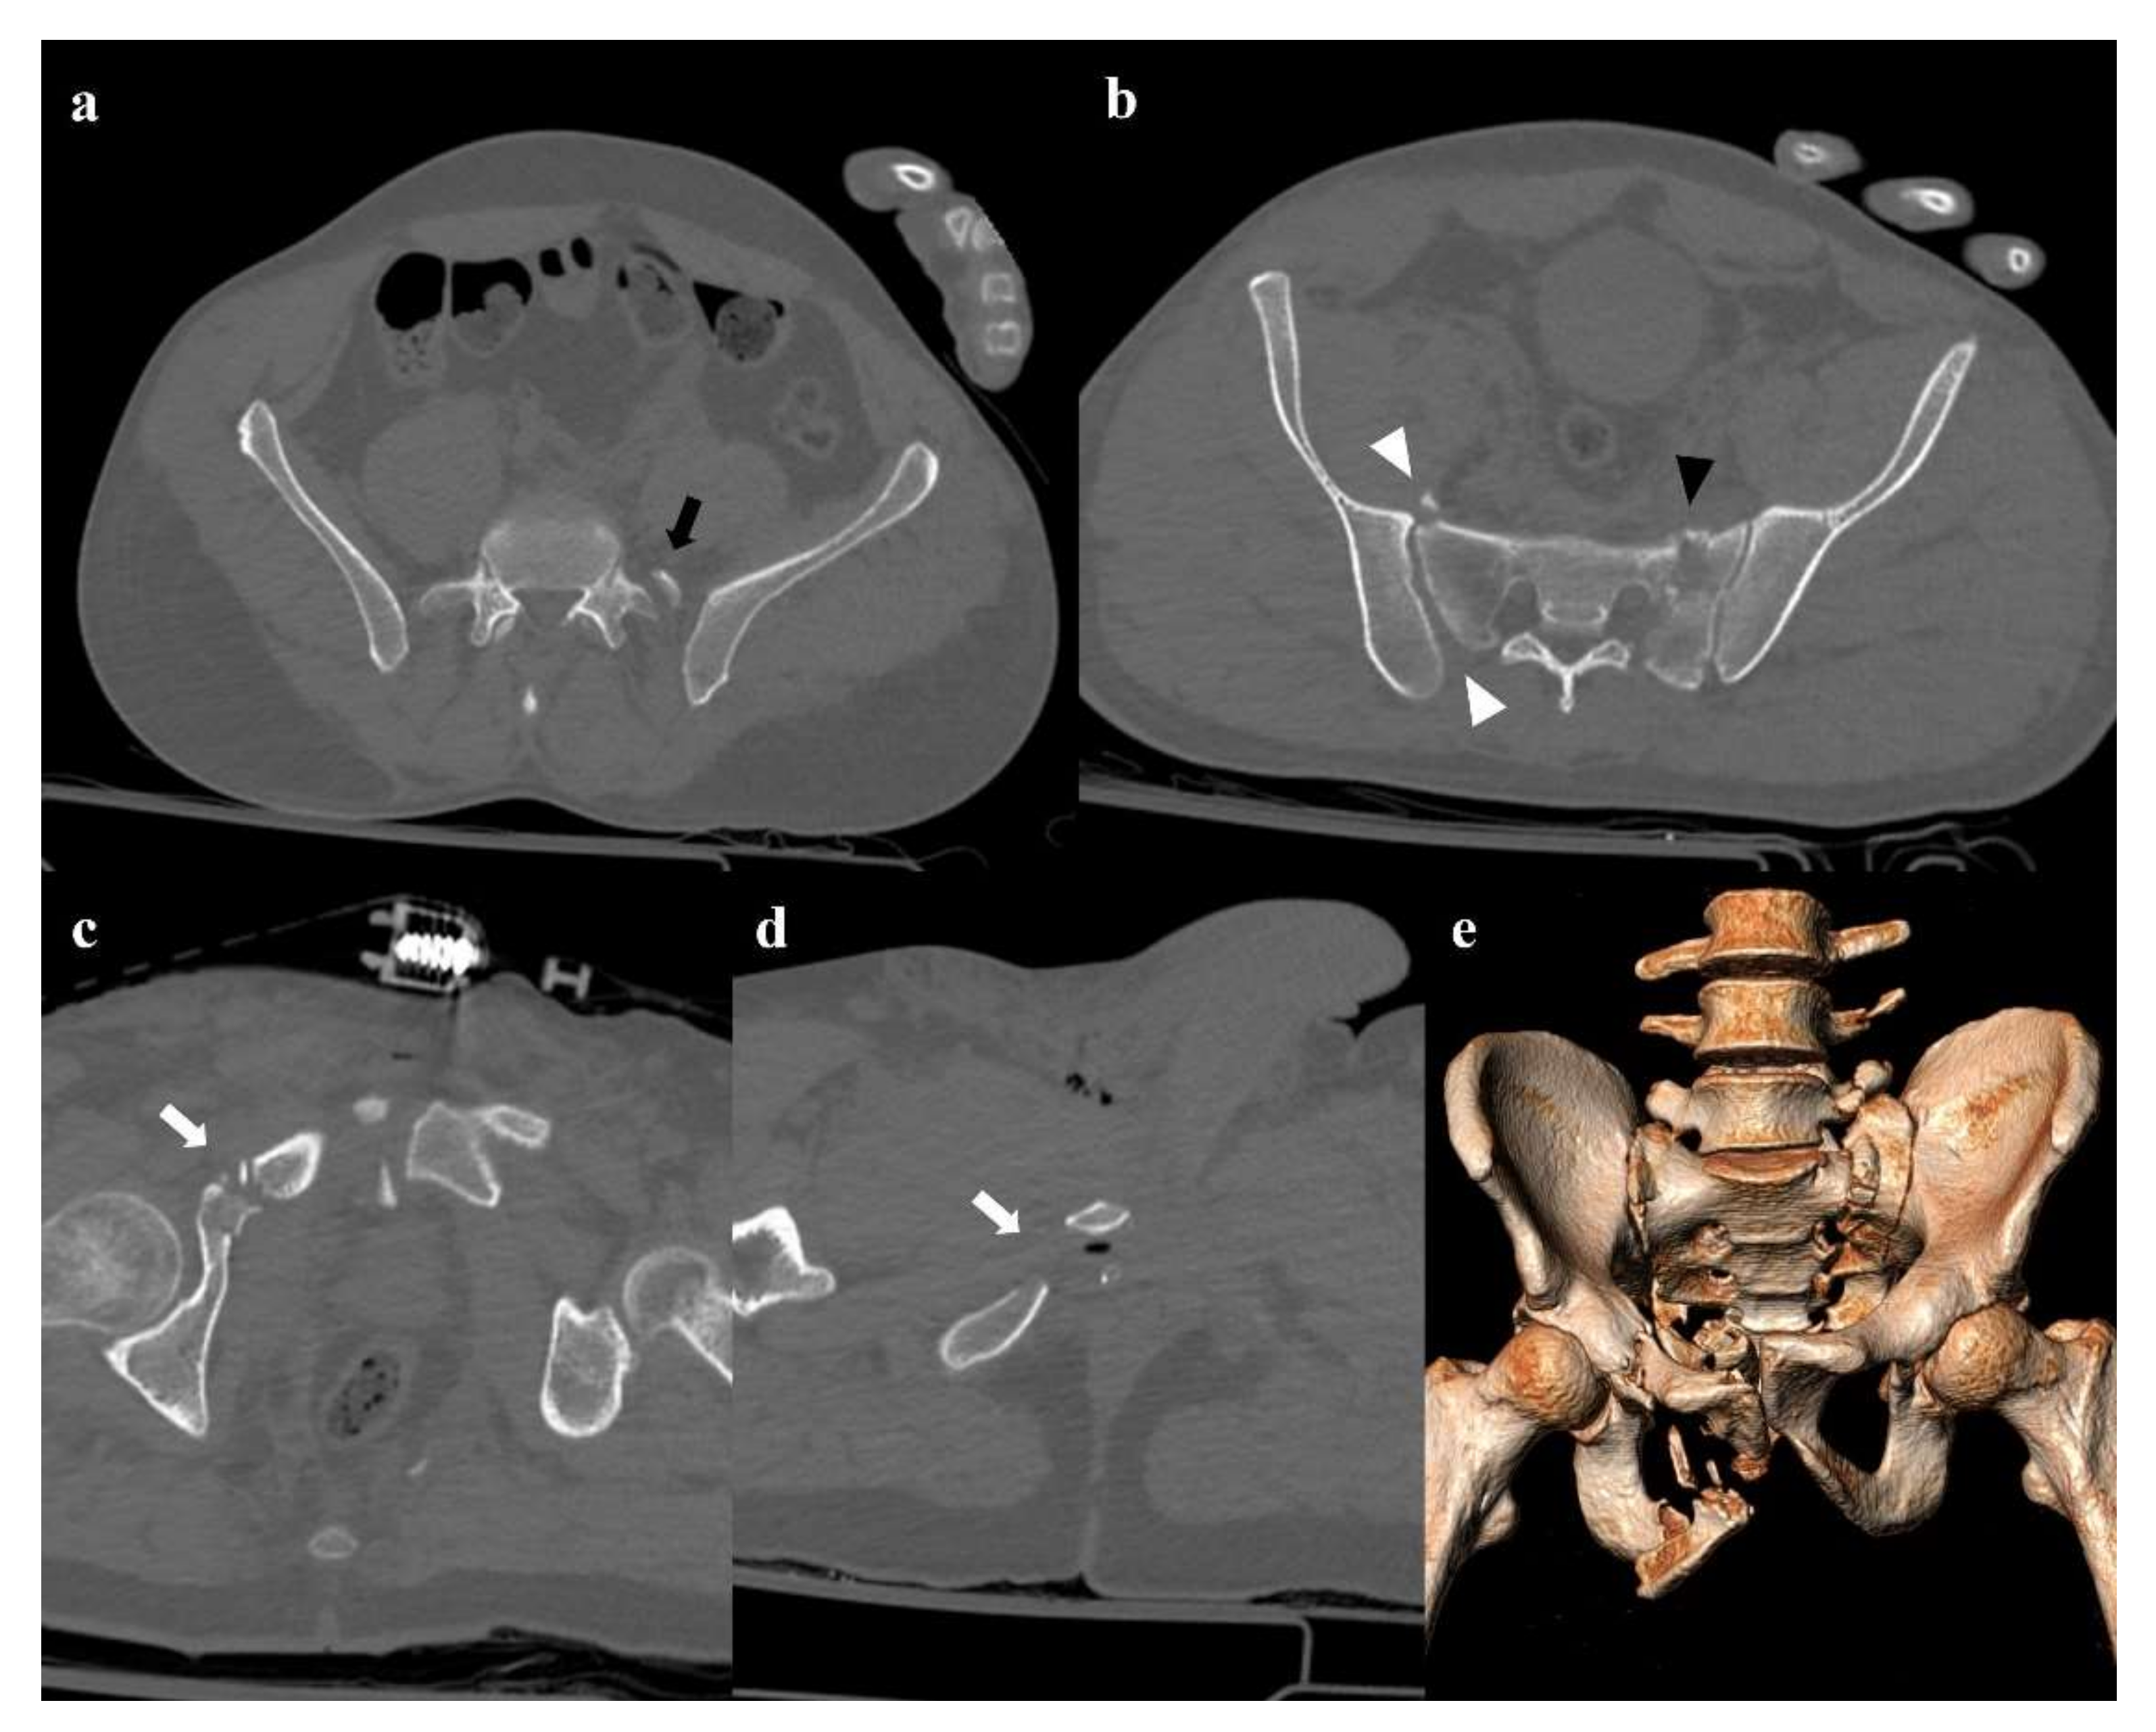

4.3.2. Anterior–Posterior Compression

- Grade 2: pubic symphysis diastasis >2.5 cm, possible vertical fracture of the pubic rami, and anterior sacroiliac joint diastasis (Figure 5). The anterior sacroiliac joint diastasis is due to the rupture of the anterior sacroiliac ligament, sacrospinous ligament, and sacrotuberous ligament. Anterior–posterior compression grade 2 injuries have a rotational instability and require a stable internal fixation [3].